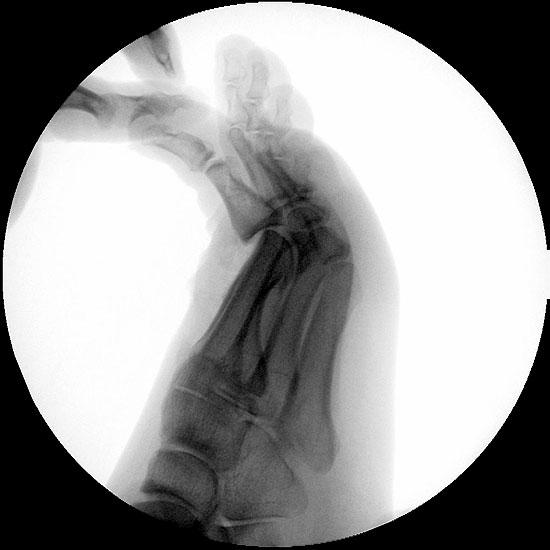

Klinisch zeigt sich stadienabhängig eine schmerzhafte Bewegungseinschränkung mit zunehmender Steifigkeit des Großzehengrundgelenkes. Vor allem die Einschränkung der Dorsalextension wird von den Patienten oft als unangenehm empfunden. Initial besteht eine bindegewebige Alteration im Gelenk, im weiteren Stadium treten Knorpeldegeneration und Begleitsynovialitis mit der Ausbildung von osteophytären Randanbauten auf. Klinische treten diese meist durch eine schmerzhafte dorsale Knochenkante in Erscheinung (Abbildung 1).

Im späten Stadium imponiert eine Gelenkblockierung durch freie Gelenkkörper. Während in den Anfangsstadien vor allem die dorsalen Anteile des Gelenks betroffen sind, betreffen die Veränderungen in den Fortgeschrittenen Stadien die gesamte Zirkumferenz einschließlich des Sesambeingleitlagers. Im Endstadium kommt es zu einer weitgehenden Ankylosierung des 1. Metatarsophalangealgelenks.

Die Cheilektomie ist indiziert vor allem im Stadium II der Erkrankung, in welchem die degenerativen Veränderungen vor allem auf die dorsalen Gelenkanteile konzentriert sind und sich in der plantaren Gelenkhälfte noch ein ausreichender Knorpelbelag findet 48. Der Eingriff umfasst die Synovektomie, die Entfernung von freien Gelenkkörpern und die Abtragung von dorsalen, lateralen und medialen Osteophyten am Metatarsale I Kopf und an der Grundgliedbasis. Zusätzlich kann eine offene Arthrolyse des Sesambeingleitlagers durchgeführt werden. Ziel ist eine Schmerzreduktion durch Abtragung der Ostepohyten mit Verbesserung der Beweglichkeit des 1. Metatarsophalangealgelenkes. Dieses Operationsverfahren kann auch im Stadium III der Erkrankung durchgeführt werden, allerdings ist dann häufiger mit Restbeschwerden und einer signifikant verlängerten Rehabilitationszeit zu rechnen 9.

• Röntgenaufnahme des Fußes in drei Ebenen unter Belastung